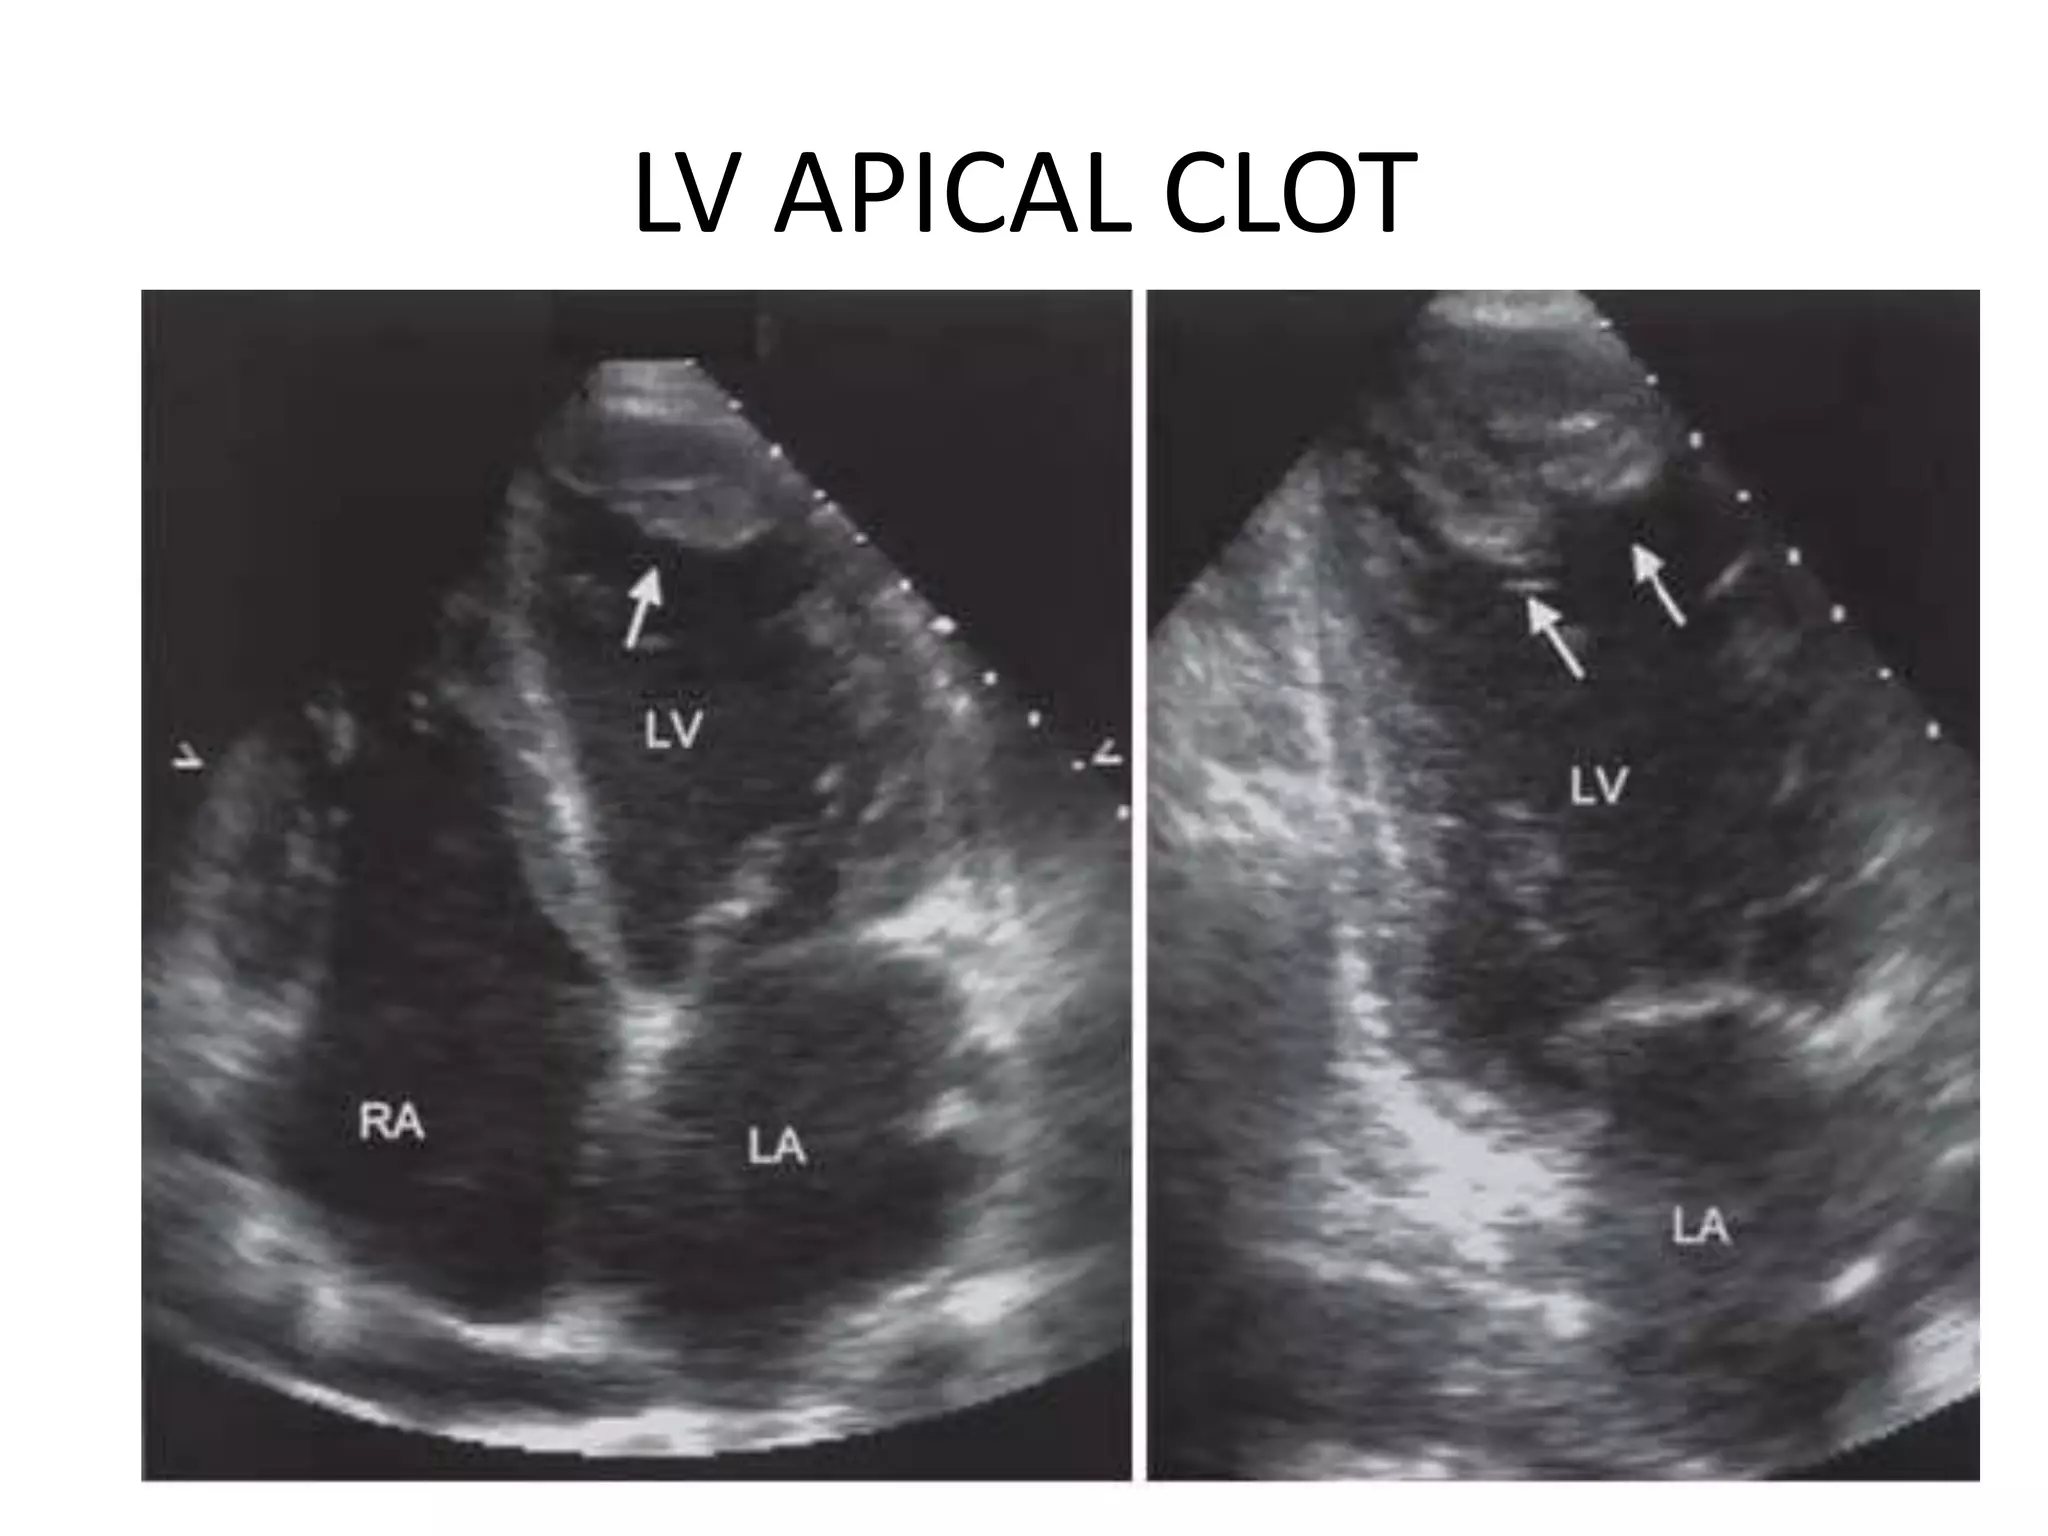

LV APICAL CLOT